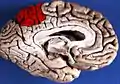

![]() Medial surface of left cerebral hemisphere. (Precuneus visible at top left.) | |

Precuneus of left cerebral hemisphere (shown in red).

Medial surface of left cerebral hemisphere. (Precuneus visible at top left.)

Medial surface of left cerebral hemisphere. (Precuneus colored in red.)